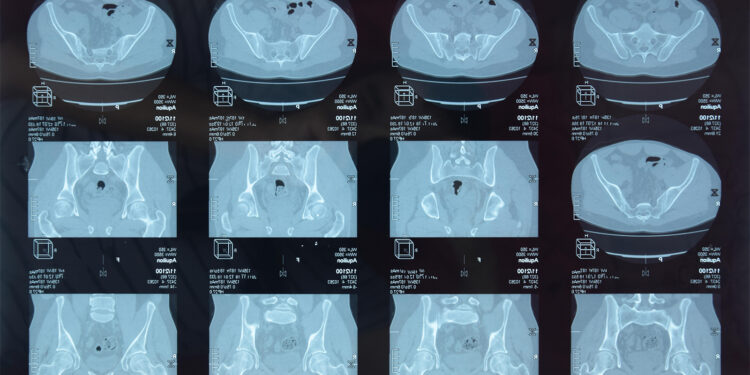

(MedPage Today) — Some 20% of people with axial spondyloarthritis (axSpA) included in a prospective cohort study showed no lesions in their sacroiliac joints, only in the spine, researchers reported — an indication that advanced imaging that…